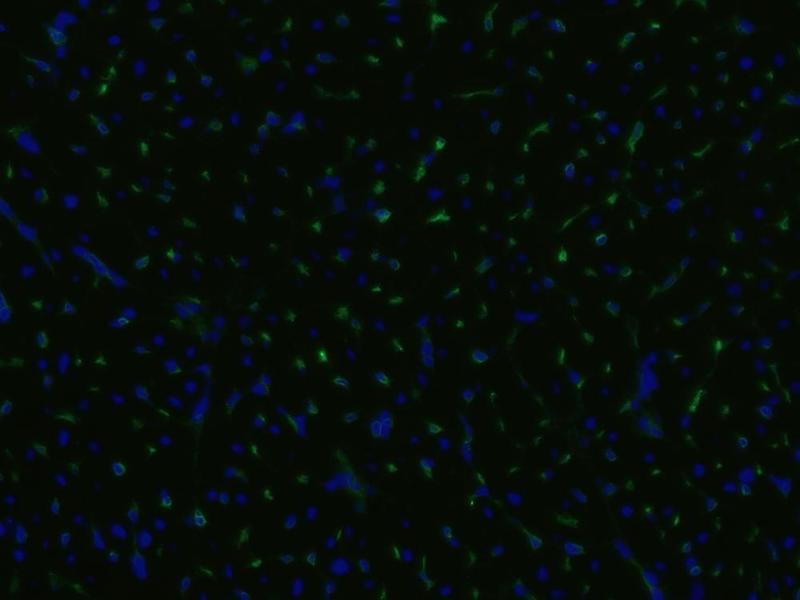

Découvrez des anticorps Endoglin fiables issus d’une large sélection de fabricants renommés. Notre portefeuille permet une détection précise de Endoglin dans plusieurs espèces, y compris Human, Mouse, Rat, Pig, Dog, Horse, Monkey, Cynomolgus, Primate, Rhesus Monkey, Guinea Pig, Rabbit, et prend en charge diverses applications de recherche telles que FACS, WB, IHC, ELISA, IF.